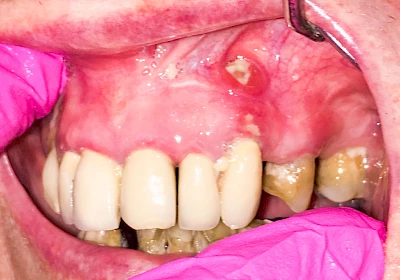

Bei einer Fistel hat sich meist eine Entzündung (manchmal auch Erreger selbst) z. B. aufgrund von Karies oder aufgrund eines Unfalls über den Zahnnerv und die Wurzelspitze (Apex) in den umliegenden Knochen ausgebreitet (apikale Parodontitis) und schnell einen Weg durch den umgebenden Knochen und die aufliegende Schleimhaut in die Mundhöhle gebahnt.

Fisteln sind in der Regel nicht schmerzhaft und fallen häufig als kleine Öffnung weiter entfernt vom Zahnfleisch nahe der Umschlagfalte auf. Aus der Fistelöffnung entleert sich spontan gelbliches Sekret (Eiter) oder es lässt sich mit dem Finger ausstreichen. Manchmal beschreiben die betroffenen Menschen immer wieder einen komischen Geschmack im Mund.

Im fortgeschrittenen Stadium kann die Schleimhaut sich weiter zurückgezogen haben und die Wurzelspitze sichtbar sein. In der Regel treten bei Fisteln keine Schwellungen auf, weil sich die Entzündung nicht im Gewebe ausbreitet.